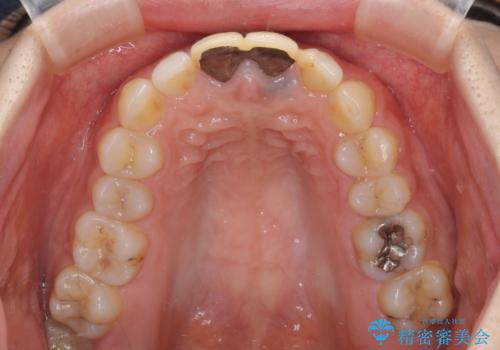

- 前歯のクラウンが着色により不自然な色となっていることを気にして来院された患者様です。

クラウンと歯の縁も合っておらず、汚れが溜まりやすい環境であったため、前歯2歯のクラウンをオールセラミッククラウンにて再補綴することとしました。